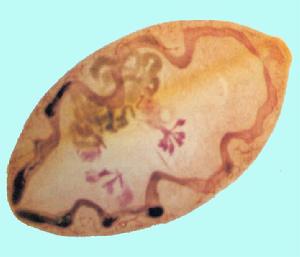

其病原是斯氏狸殖吸蟲。成蟲蟲體窄長,蟲體最寬處約在前1/3或稍後,大小為3.5~6.0mmⅹ11.0-18.5mm,腹吸盤位於體前約1/3處,略大於口吸盤。卵巢位於腹吸盤的後側,其大小及分支情況與蟲齡有密切關係,蟲齡高者分支數多,形如珊瑚。睪丸2個,左右並列,分葉數變異較大,長度占體長的1/7~1/4,甚至可達1/3。蟲卵橢圓形,大多數形狀不對稱,殼厚薄不均勻,大小平均71ⅹ48mm,在不同地區、宿主等存在一定差異。